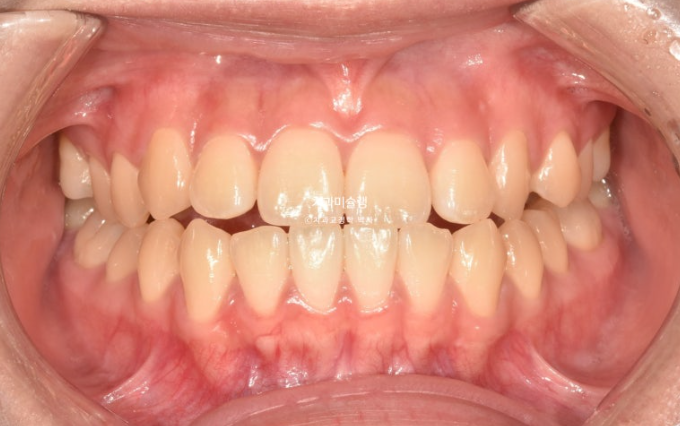

25.07

중심선은 정확히 맞고

양측 어금니는 1급 교합 관계를 보입니다.